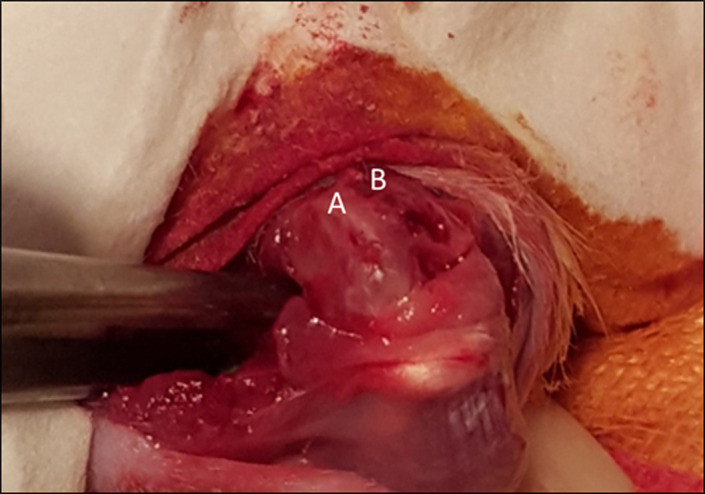

Methods: A total of 24 Wistar albino rats were used in this study, and one hind leg of each animal was operated on, while the other served as a control. A 2-step surgical procedure was performed: First, a microfracture was generated at a 2 mm × 2 mm cartilage defect area in the medial condyle of the femur after a left knee arthrotomy. Second, 6 weeks later, after a double knee arthrotomy, fibrocartilage from the microfracture area of the left knee and 2 × 2 mm of hyaline cartilage from the medial femoral condyle of the right knee were harvested. Chondrocytes were isolated and grouped as HCh or FCh, and cell viability and apoptosis were determined by MTT (4,5-dimethylthiazol -2-yl)-2,5-diphenyltetrazolium bromide) and caspase-3 assays using enzyme-linked immunosorbent assay (ELISA) kits.